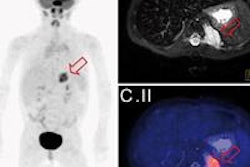

Fusion image of LGE MRI and PET in a four-chamber long-axis (left panel) view and a short-axis view (right panel) in a 60-year-old man with ST segment elevation myocardial infarction (STEMI) because of a proximal occlusion of the left anterior descending (LAD) artery. MRI revealed a transmural infarction within nearly the entire septum and the apex of the left ventricle (late gadolinium enhancement with an area of no-reflow), whereas a corresponding area of reduced tracer uptake can be seen in the perfusion territory of the LAD. The fusion images also demonstrate a significantly larger defect of FDG uptake (reduced viability) than the extent of the late gadolinium enhancement image. All images courtesy of Dr. Ercan Tezgah."We think you should combine PET and MRI because MRI shows really the infarction but PET might show us the ischemic zone of the myocardium, which is not really infarcted now," said cardiologist and lead author Dr. Ercan Tezgah in an interview with AuntMinnieEurope.com.

In their study of 25 patients with a wide range of myocardial infarction types, imaging with PET/MRI found significant correlation between the PET part of the exam and late gadolinium enhancement (LGE) MRI scans, as long as the infarction was large enough to be transmural, the investigators found. PET routinely showed larger regions of ischemia than late gadolinium enhancement at MRI, potentially highlighting myocardial tissue at risk that could be protected using the right techniques.

In 24 of 25 patients (96%), PET % (31 ± 11%) was even larger than LGE % (10 ± 10%) -- a difference that was highly significant (p < 0.0001).

And as stated, almost a quarter of the patients (6/25, 24%), the myocardial infarction was confirmed by reduced glucose metabolism as shown in PET % (32 ± 5%), even though no LGE was detectable at MRI, the investigators found.